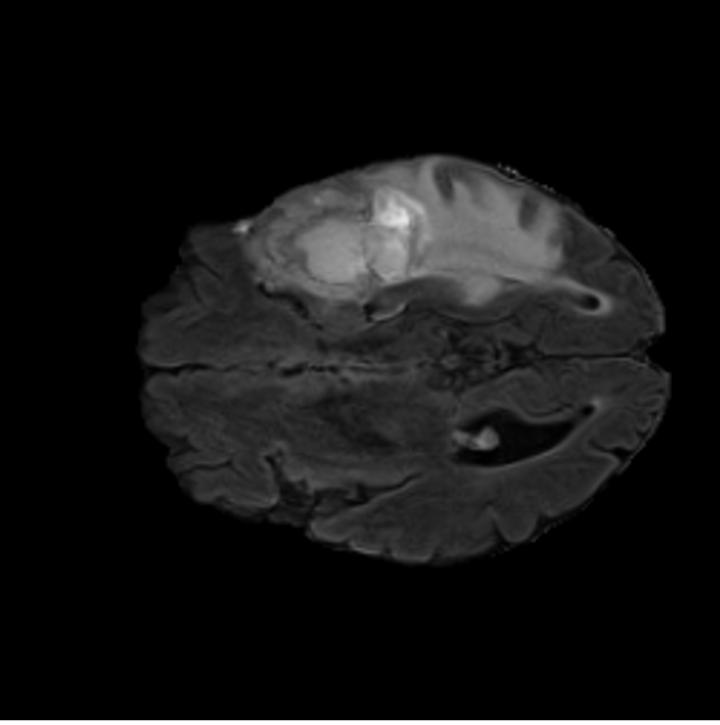

Notably, X-Diffusion achieves sota dB for a few input slices while baselines require more than 60 input slices to achieve similar performance (Figure 7). The margin is more than 12 dB PSNR for the 1-slice input in both the BRATS and the UK Biobank benchmarks (see Table 1 and Figure 6). For reference, two randomly sampled MRIs from the UK Biobank would have a PSNR of 15.95 dB 0.36 (on 4800 randomly sampled examples). The slices from 3D reconstructed volumes at varying depths and axis of rotation visually match the ground truths (see Figures 5 and Figure 4). We also plot the error map (Figure 4) of such X-Diffusion generations to highlight the differences with the ground truth MRIs.

5.3 Out-of-Domain Generalisation

One way to test the generalization capability of the trained X-Diffusion is to test it on a completely different domain from an MRI dataset not seen during training. We report the single-slice results on the test set of knees from NYU fastMRI [33, 80], using the X-Diffusion trained on the BRATS brain MRIs. The test PSNR result is 34.17 and an example is shown in Figure 8. It shows how successfully X-Diffusion can generate knee MRIs (out-of-domain) despite being trained on brains.